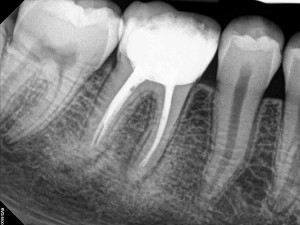

after the root canal has been completed on the tooth.